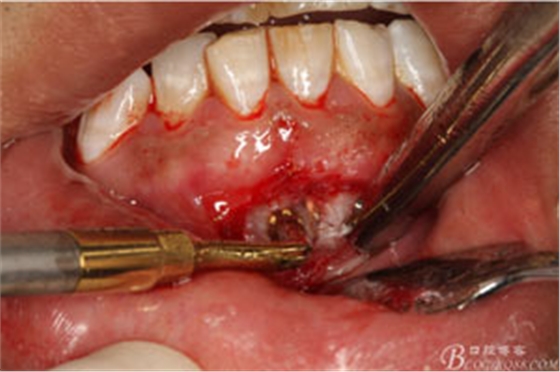

圖8.超聲骨刀去除根尖周圍感染骨質(zhì)